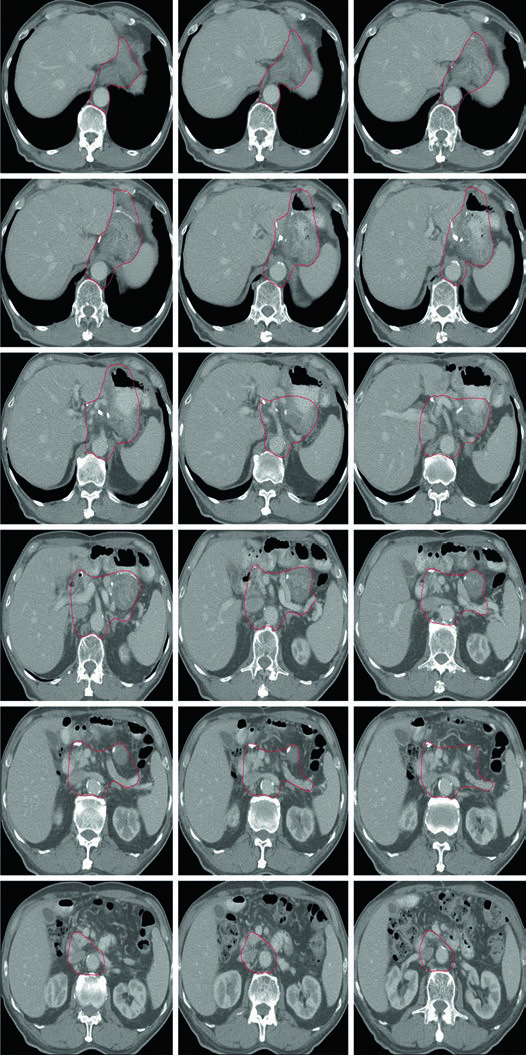

Caso 2: T3N3M0 Adenocarcinoma do Corpo — Gastrectomia Distal

Com doença T3N3, o CTV é extenso: inclui anastomose gastrojejunal, estômago remanescente, artéria celíaca, hilo esplênico e leito tumoral pancreático. Esse cenário exige atenção especial às restrições de dose nos órgãos de risco — particularmente rins e fígado — pois o volume de tratamento é considerável.